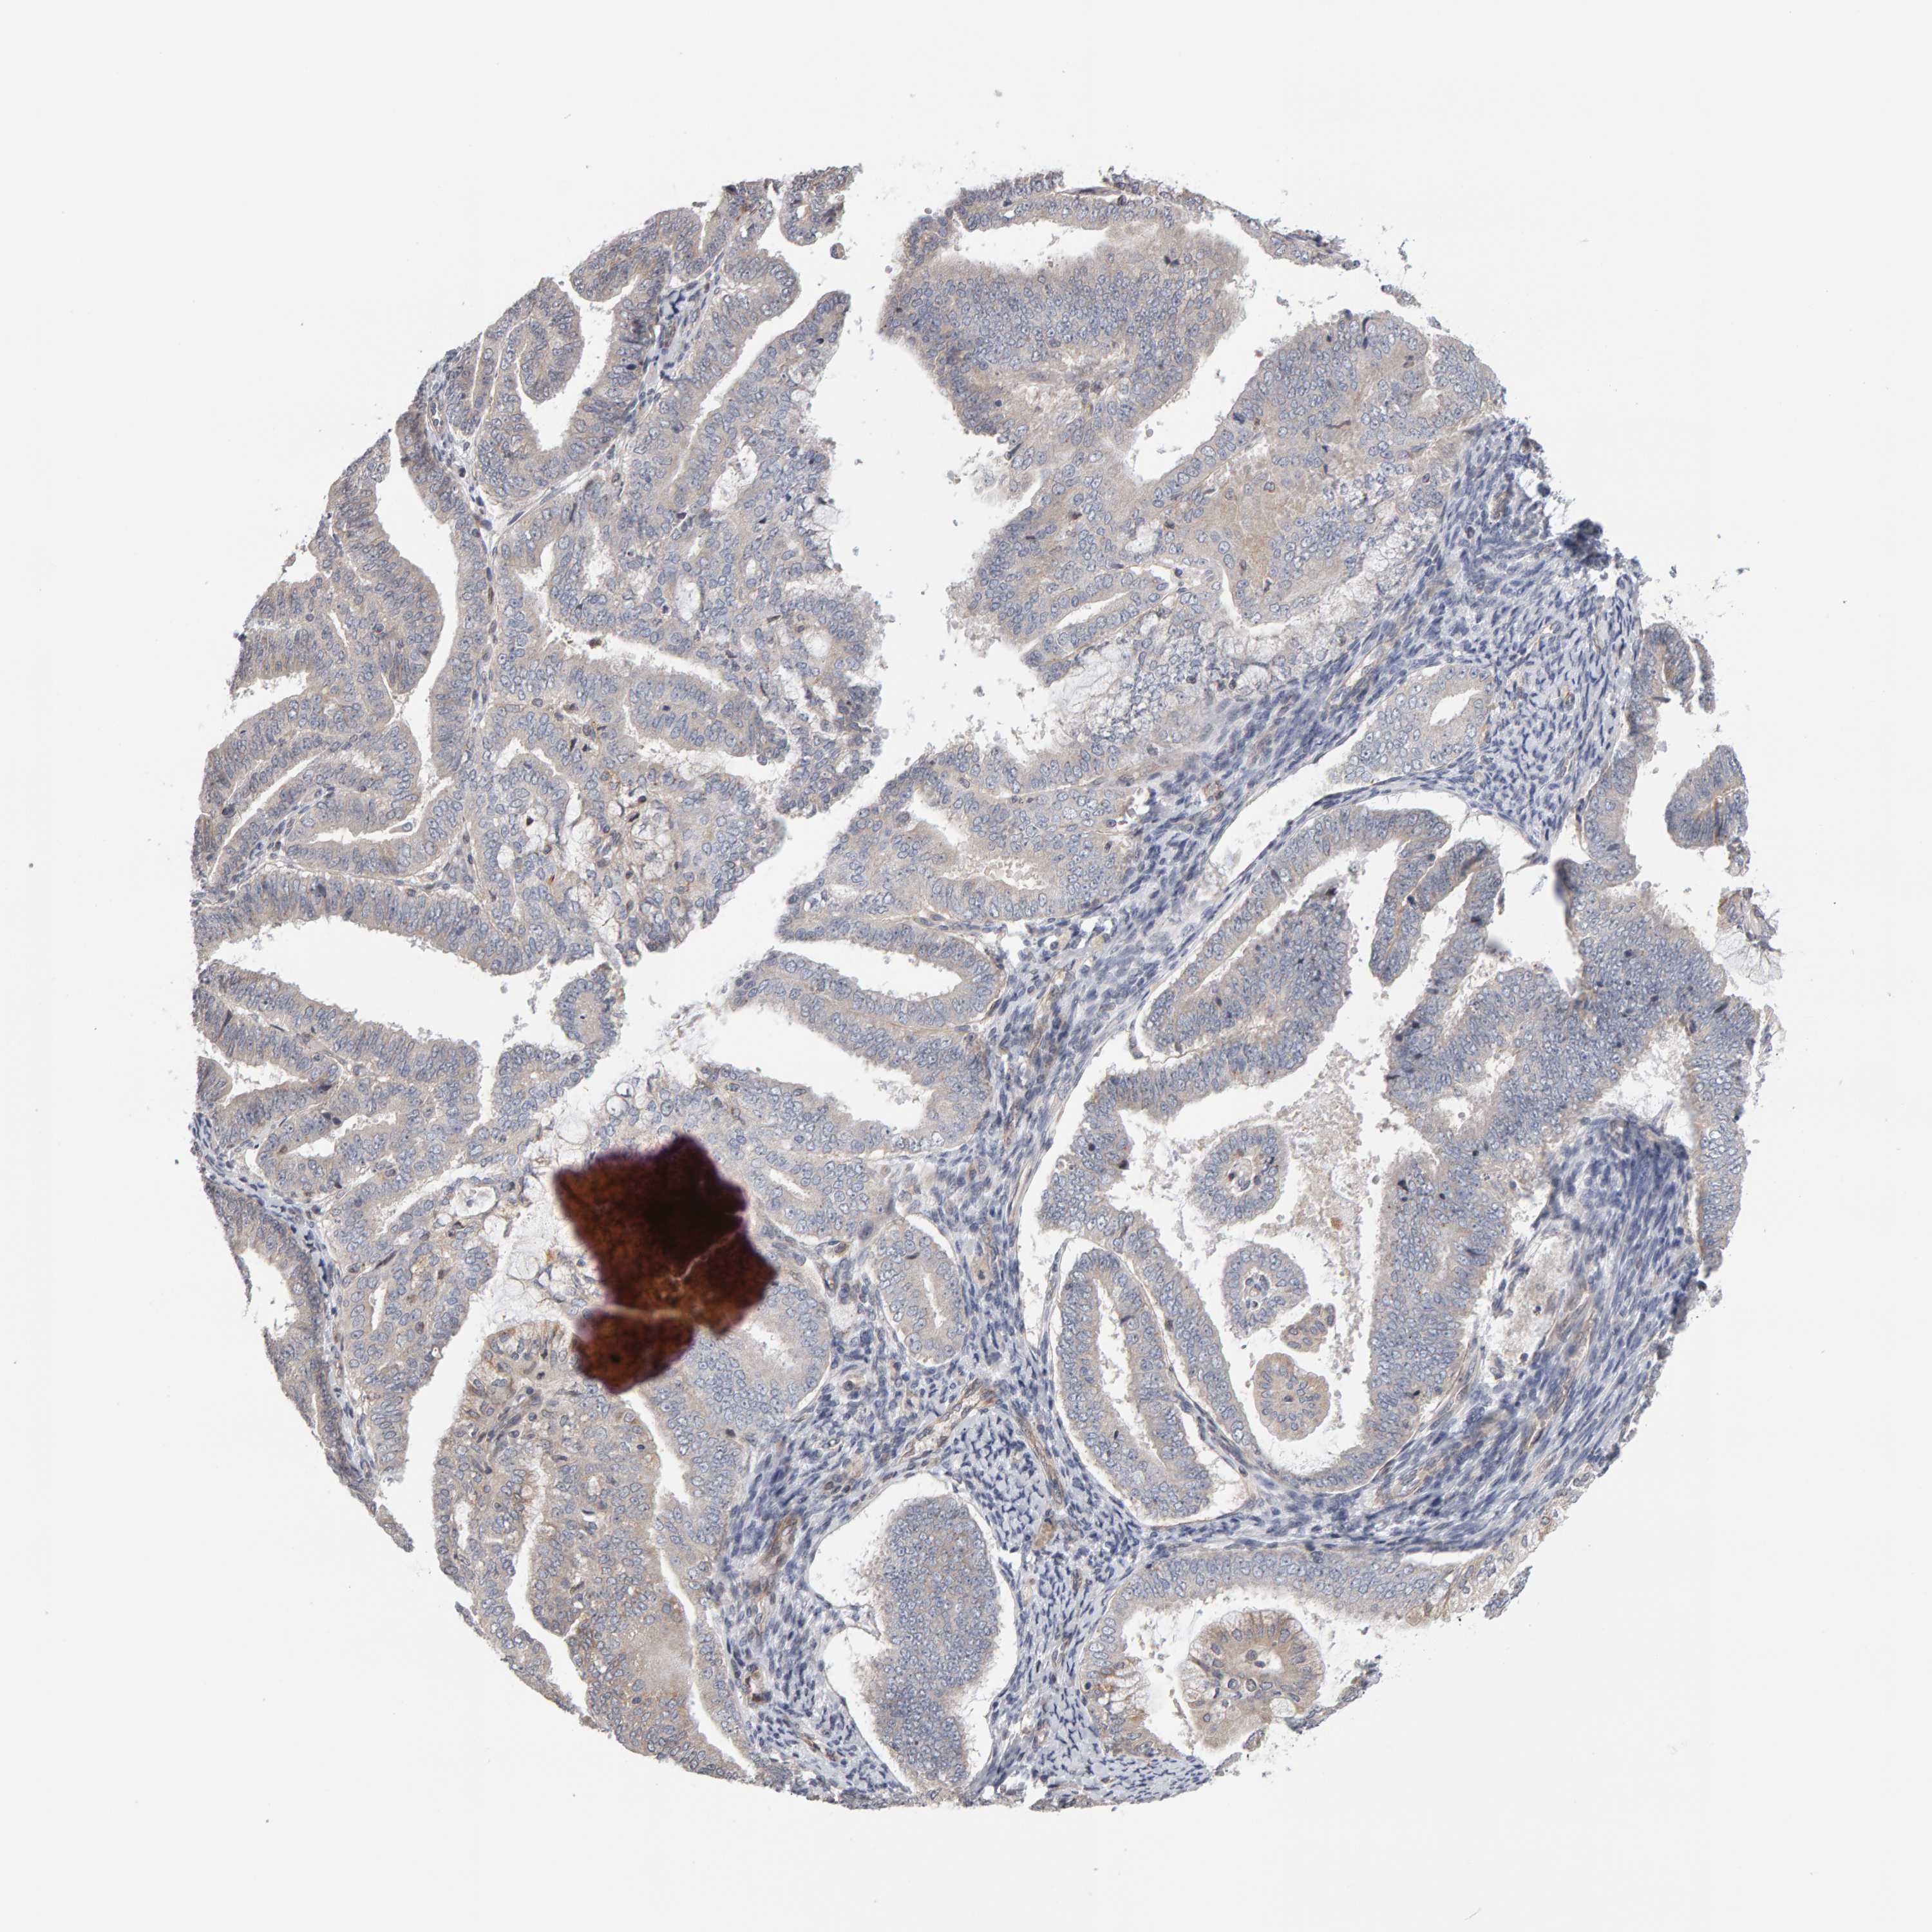

ENDOMETRIAL CANCER - Protein expressioni

A mouse-over function shows sample information and annotation data. Click on an image to view it in a full screen mode. Samples can be filtered based on level of antibody staining by selecting one or several of the following categories: high, medium, low and not detected. The assay and annotation is described here.

Note that samples used for immunohistochemistry by the Human Protein Atlas do not correspond to samples in the TCGA dataset.

Antibody stainingi

Antibody staining in the annotated cell types in the current human tissue is reported as not detected, low, medium, or high, based on conventional immunohistochemistry profiling in selected tissues. This score is based on the combination of the staining intensity and fraction of stained cells.

Each image is clickable and will lead to virtual microscopy that enables deeper exploration of all samples and also displays staining intensity scores, fraction scores and subcellular localization as well as patient and tissue information for each sample.

Antibody HPA023804

Antibody HPA075766

Staining

High

Medium

Low

Not detected

Intensity

Strong

Moderate

Weak

Negative

Quantity

>75%

75%-25%

<25%

None

Location

Nuclear

Cytoplasmic/membranous

Cytoplasmic/membranous,nuclear

Adenocarcinoma, NOS

Adenoma, NOS